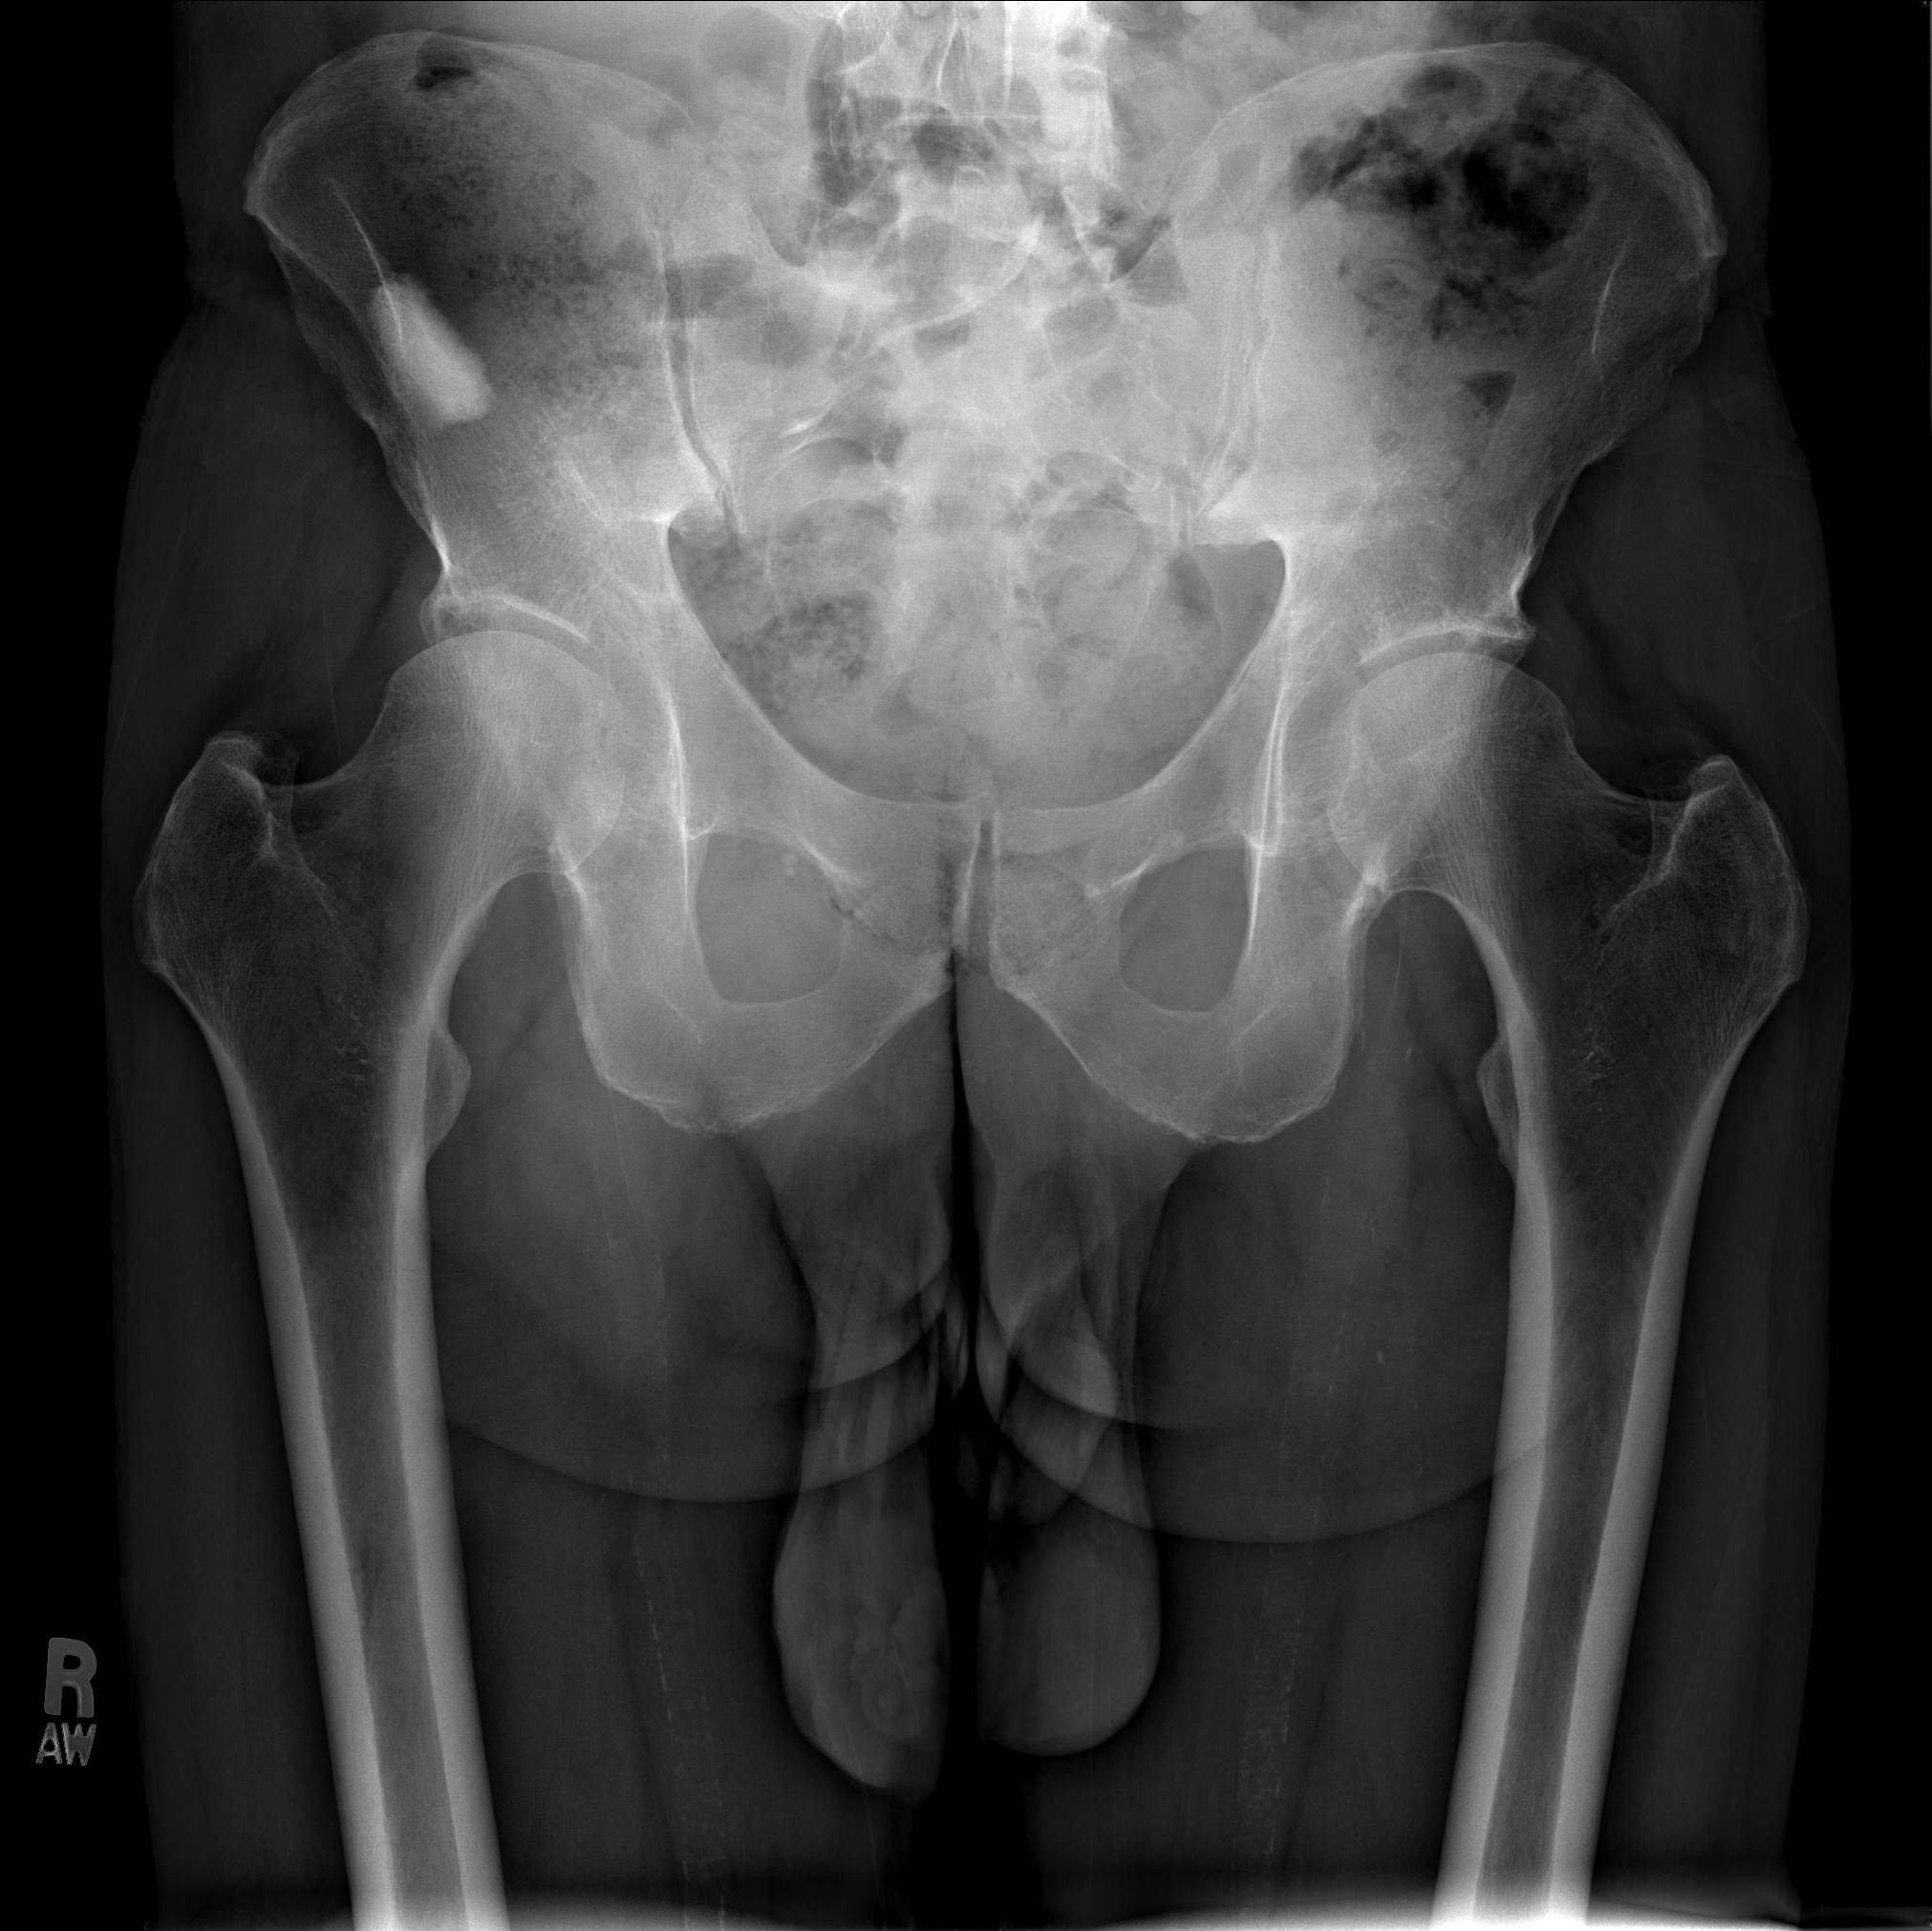

1. Right lung mass with multiple bilateral pulmonary nodules. 32 mm x 17

mm sclerotic lesion within the right iliac bone. This likely represents a

primary lung cancer with metastatic lesion to the pelvis.